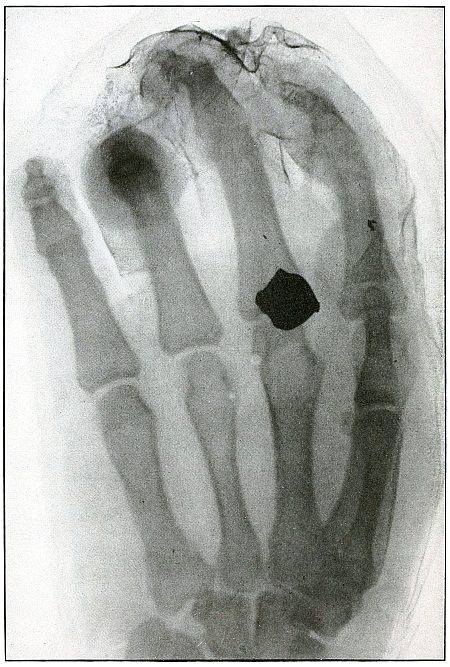

Rifle—Plate 43.

Gunshot Fracture of the Metacarpus.

Wound of entrance, inner aspect of the hand over proximal end of the fifth metacarpal.

Wound of exit, on the outer border of the hand over the distal end of the second metacarpal.

The velocity of the bullet was in mid or long range, as it displaced no fragments, and as it made a point of entrance and exit about the same in appearance.

The wound was infected, which is more frequently the case in the hand than in the forearm.

The treatment is conservative with free incision and drainage in the management of infection. [Pg 98]